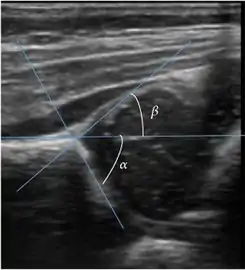

Ultrasound allows categorizing pediatric hips, according to Graf’s criteria, in four main types: normal, immature, and dysplastic (subluxed and dislocated). This classification is based on measurements of the acetabular inclination angle (alpha), cartilage roof angle (beta), and infant age. The femoral head coverage can also be determined by dividing the length of the femoral head covered by the acetabular fossa and the diameter of the femoral head. Its lower normal limits are 47% for boys and 44% for girls (Figure 11).[1]

Figure 11:

Useful ultrasound measures in neonatal hip sonography, alpha and beta angles.[1]